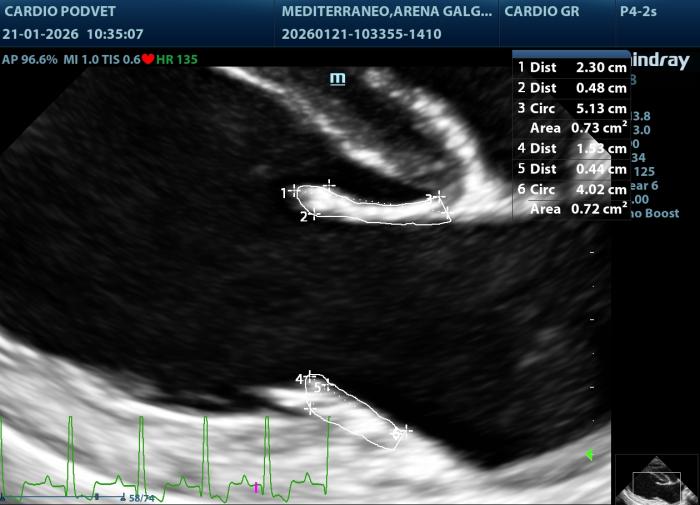

Posteriormente se obtiene este índice mediante la siguiente fórmula: LAI= AML (mm) + PML (mm)]/APL(mm). El área mitral se calcula obteniendo los diámetros de la válvula mitral (AM) en la vista paraesternal derecha transversal a la altura de la válvula mitral, con los diámetros anteroposterior (dAP) y diámetro transcversal (dT) (Figura2) y la fórmula: AM = (π x (dAP/2) x (dT/2))/100. Y por último los diámetros y áreas de las valvas mitrales medidas en la vista paraesternal derecha 4 cámaras durante la diástole (Figura3A-B).